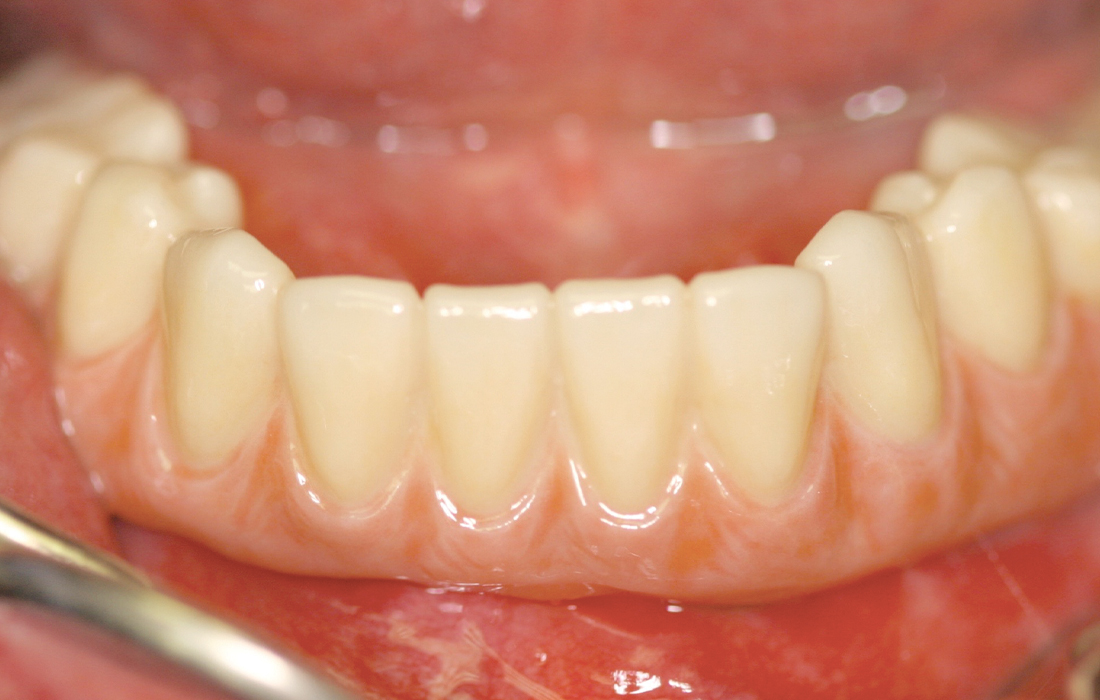

This patient presented with terminal dentition due to extensive caries and advanced periodontal disease. After removing the patient’s remaining teeth, Hahn Tapered Implants were placed during the same appointment to support a fixed restoration, and healing abutments were delivered. Four months later, a monolithic zirconia full-arch restoration was delivered, providing the patient with renewed function, esthetics and quality of life.